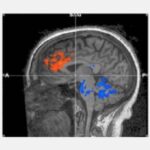

Паттерны функционального МРТ(ФМРТ) во время практики Трансцендентальной Медитации показали, что, как и в медитациях, требующих концентрации наблюдается повышенная активность в областях префронтальной коры, связанных с вниманием, что указывает на бдительность. Однако, в отличие от других медитаций, во время Трансцендентальной Медитации также снизилась активность в областях, связанных с возбуждением, что указывает на глубокий отдых.

По сравнению с простым отдыхом с закрытыми глазами, сканирование с помощью функционального МРТ обнаружило увеличение кровотока в двусторонней передней поясной извилине и двусторонней дорсолатеральной префронтальной коре – областях префронтальной коры головного мозга, связанных с вниманием и исполнительными функциями, такими как принятие решений, рассуждение, рабочая память, торможение и ожидание вознаграждения.

Однако, в отличие от других медитаций, во время Трансцендентальной Медитации наблюдалось уменьшение притока крови к мосту и мозжечку. Мост модулирует общее состояние возбуждения человека и регулирует дыхание и частоту сердечных сокращений. Снижение активности в этой области мозга поддерживает ощущения во время Трансцендентальной Медитации глубоко безмолвного ума и отдохнувшего тела.

Мозжечок регулирует скорость и вариативность обработки информации, связанной как с координацией и контролем моторики, так и с когнитивными функциями, такими как внимание и речь. Снижение активности предполагает, что тело возвращается в более автоматический режим без необходимости когнитивных усилий для осуществления контроля.

По словам доктора Трэвиса, вместе снижение активности мостов и мозжечка предполагает общее снижение когнитивного контроля и исполнительной обработки во время Трансцендентальной Медитации – как будто система внимания находится в точке баланса, готовой действовать в любой момент, когда это необходимо.